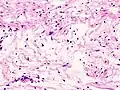

Illustrations

Neurinome subcutané_Antoni_B.jpg)

_Antoni_B.jpg)